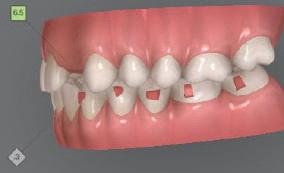

Dental Tribune Bulgarian Edition / октомври 2022 г.16 клиничен случай с алайнери Г орният латерален ре зец е вторият найчесто вродено липсващ зъб.1,2 Поради разполо жението му във видимата зона на усмивката лечение то на подобни случаи нала га мултидисциплинарен под ход, целящ отличен функцио нален и естетичен резултат. Налице са няколко лечебни мо далности, свързани с различ но разпределение на място то: първият вариант е орто донтско отваряне на място и възстановяване на липсва щия зъб с конструкция, под държана от съседните зъби3 или от имплант4, докато при втория подход разстоянията се затварят и премоларът заема мястото на канина.5 Изборът на лечебен подход трябва да бъде направен съв местно от зъболекар и паци ент въз основа на очакванията на последния и предвиди мостта на лечението. Множе ство фактори влияят върху това решение, като напри мер типа малоклузия, размера, формата и цвета на кучеш ките зъби6, оклузалните вза имоотношения (овърджет и овърбайт), лицевия профил, дължината на зъбната дъга и несъответствията в разме ра на зъбите.7 В настоящата публикация се разглежда случаят на жена в зряла възраст с вродена лип са на горен ляв латерален резец. Бяха приложени про зрачни алайнери за отваряне на място за единичен им плант и бяха постигна ти функционална оклузия и отлична естетика. ПРЕДСТАВЯНЕ НА СЛУЧАЯ Диагноза Пациентката бе на 32 годи ни, когато лечението започна, и първоначалното ѝ състоя ние бе следното (фиг. 1–3): липсващ горен ляв латерален резец; клас II, подклас I малоклузия; отклонение на горната сре динна линия вляво; Доклад на клиничен случай ЛЕЧЕНИЕ С АЛАЙНЕРИ НА ПАЦИЕНТ С АГЕНЕЗИЯ НА ЛАТЕРАЛЕН РЕЗЕЦ Д-р Iro Eleftheriadi и д-р Christodoulos Laspos, Гърция и Кипър Фиг. 1a–h Предоперативни лицеви и интраорални снимки. Фиг. 2a–e Дигитални модели преди началото на лечението. Фиг. 3 Панорамна снимка преди лечението. Фиг. 1a Фиг. 1d Фиг. 1f Фиг. 2a Фиг. 2d Фиг. 2b Фиг. 2e Фиг. 3 Фиг. 2c Фиг. 1b Фиг. 1e Фиг. 1g Фиг. 1h Фиг. 1c

Цели на лечението и лечебен план Целите на лечението бяха следните: нивелиране и подреждане на зъбите и в двете зъбни дъги; отваряне на пространство за липсващия латерален резец; коригиране на отношенията при канините и моларите до клас I; и корекция на отклонението на срединната линия. Лечебният план включваше: корекция на отношенията при кучешките зъби и мола рите до клас I с дистализира не на максилата; отваряне на пространство в областта на #22 за поставя не на единичен имплант; корекция на срединната ли ния; и създаване на място за раз ширяване на зъб #12 и апрок симална редукция в долната челюст с цел подобряване на несъответствието по Болтън и осигуряване на подобра оклузия. Изпълнение на лечебния план Този случай бе изпълнен със системата за алайнери Invisalign (Align Technology). Одобреният първоначален лечебен план предвиждаше 49 алайне ра с дистализиране на задни те горни зъби до клас I (прибли зително с около 3.5 мм; фиг. 5). За бъдещия имплант в областта на липсващия латерал бе планирано пространство от 6.5 мм, докато във фронталния сегмент на долната челюст бе предвидена апроксимална редук ция. В дясната страна бутон за ластици клас II бе поставен на зъб #47 вместо на зъб #46, за да не се увреди короната на импланта. Понеже пациентката жи вееше в чужбина,

следните казуси: недобра оклу зия в дисталните зони по вре ме на дистализирането на гор ната челюст и накланяне на зъб #21 (фиг. 7). Последното се дължи на липсата на компози тен атачмънт на този зъб, каквото не бе зададено в пър Фиг. 4 Телерентгенография и цефалометричен анализ преди началото на лечението. Фиг. 5a–e Одобреният първоначален лечебен план. Фиг. 6a–h Снимки по време на лечението, показващи нуждата от внасяне на някои корекции. Фиг. 4 Фиг. 5a Фиг. 5d Фиг. 6a Фиг. 6d Фиг. 6f Фиг. 6b Фиг. 6e Фиг. 6g Фиг. 6h Фиг. 6c Фиг. 5e Фиг. 5b Фиг. 5c